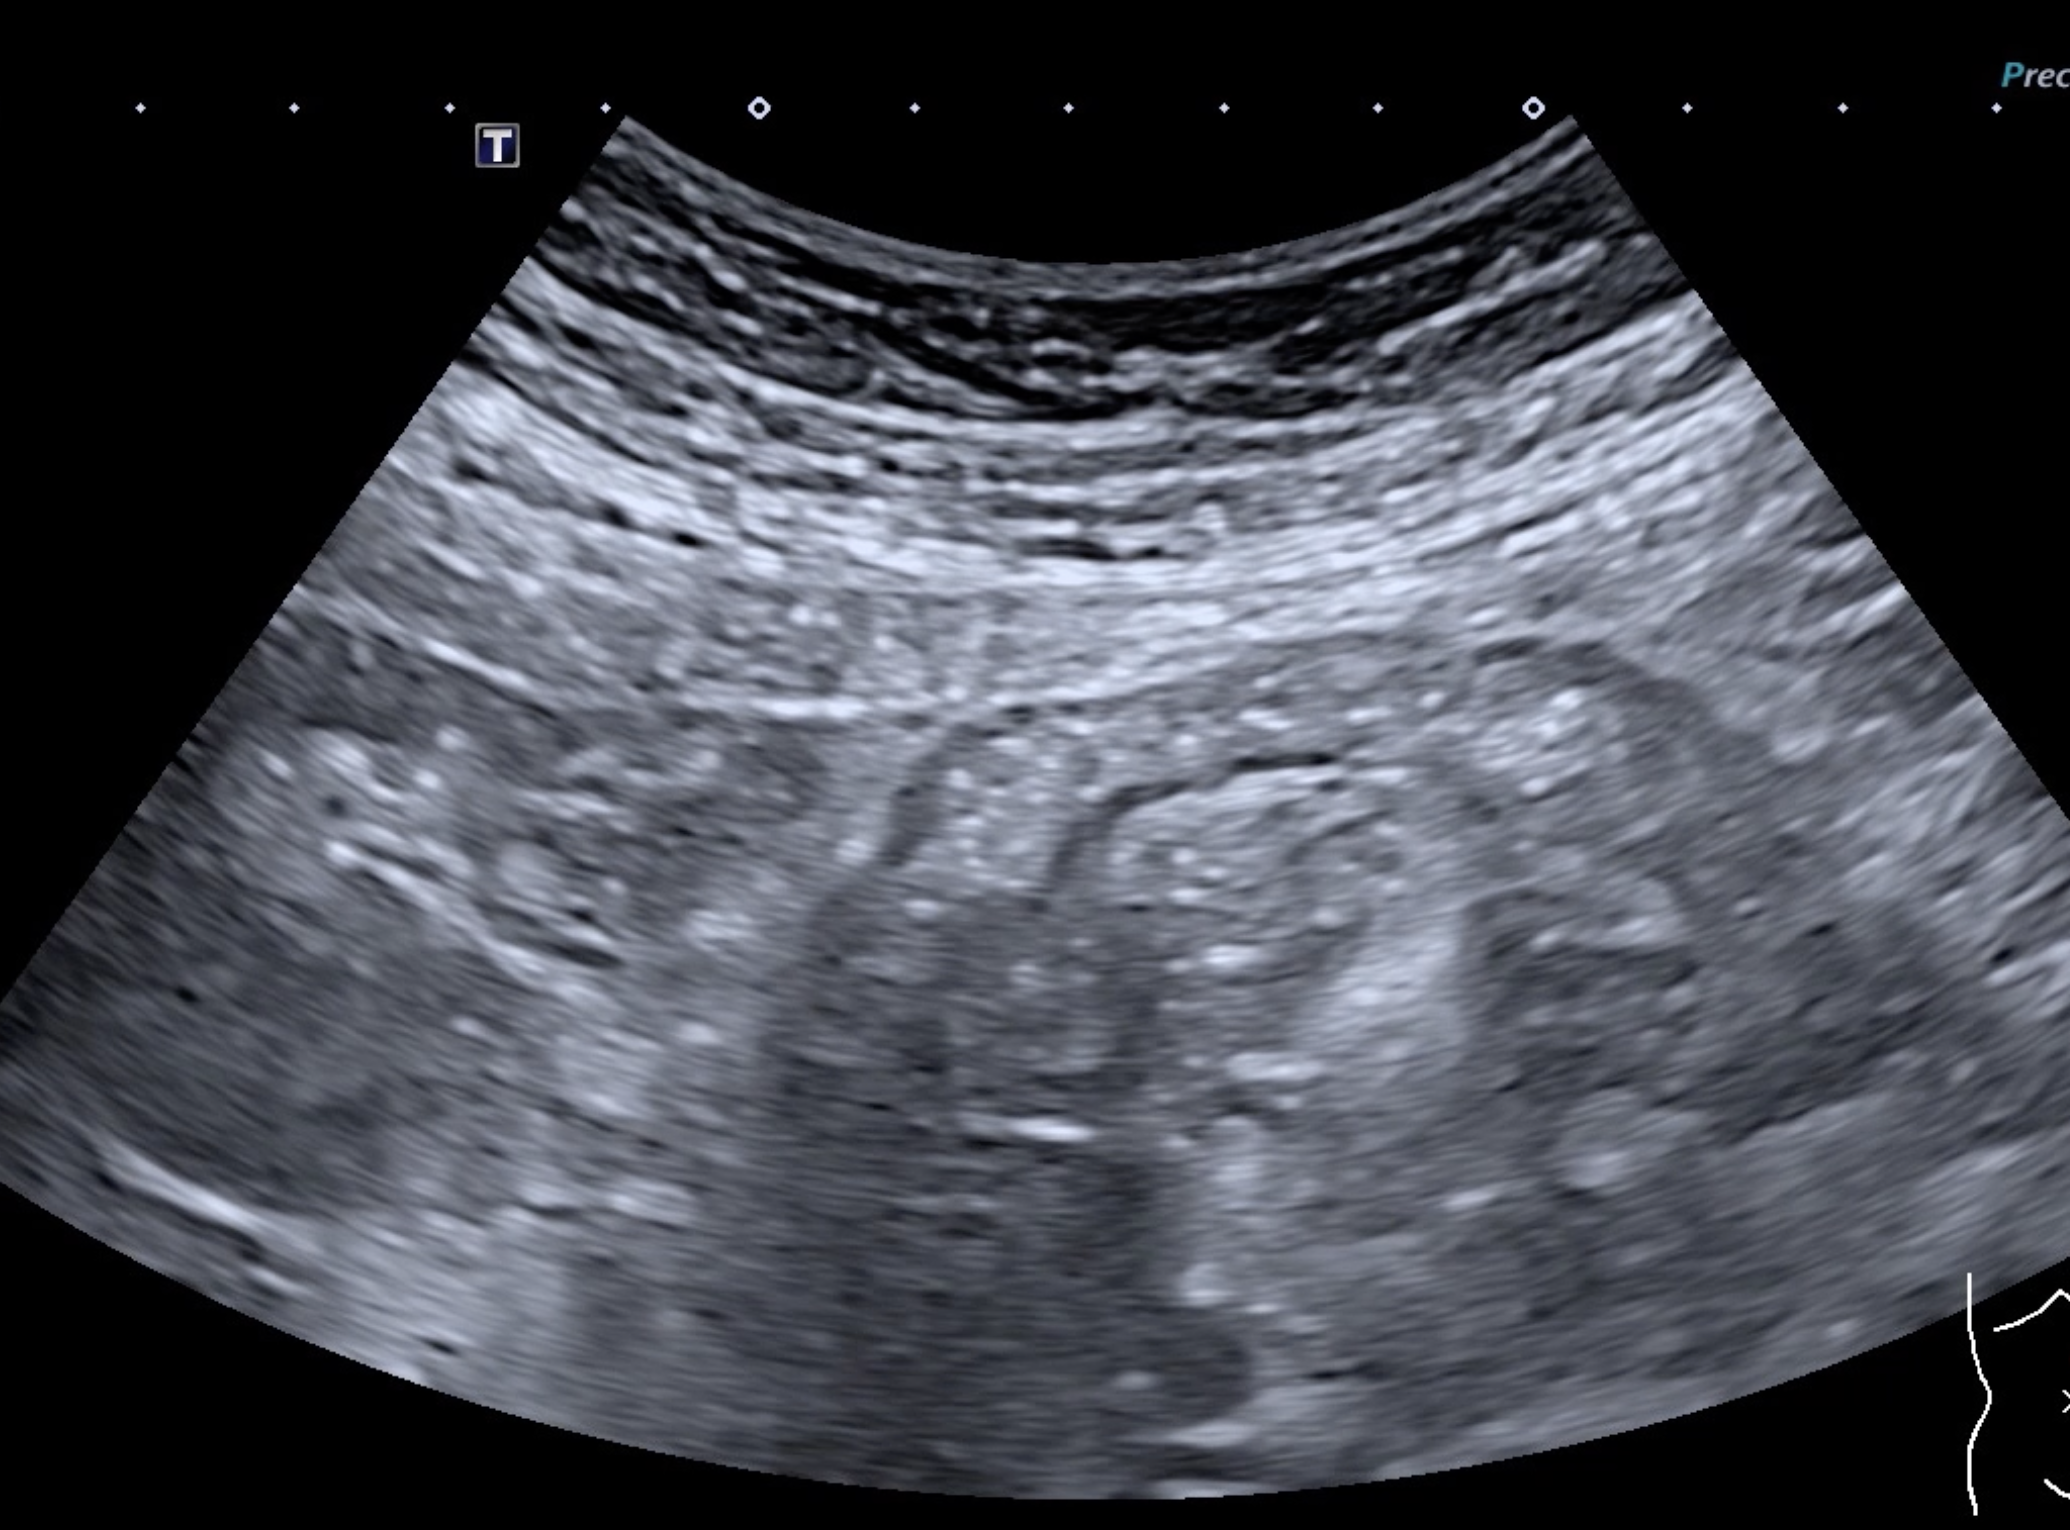

La paroi est redevenue strictement normale, rien ne permet de la différentier d’un colon sain.

L’épaisseur pariétale est de 1,8 mm, structure en couche totalement rétablie, le Doppler est négatif, Limberg 0.

On retrouve les haustrations coliques normales.

Le score de Milan est de (1,8 x1,4+0) MUC = 2,52